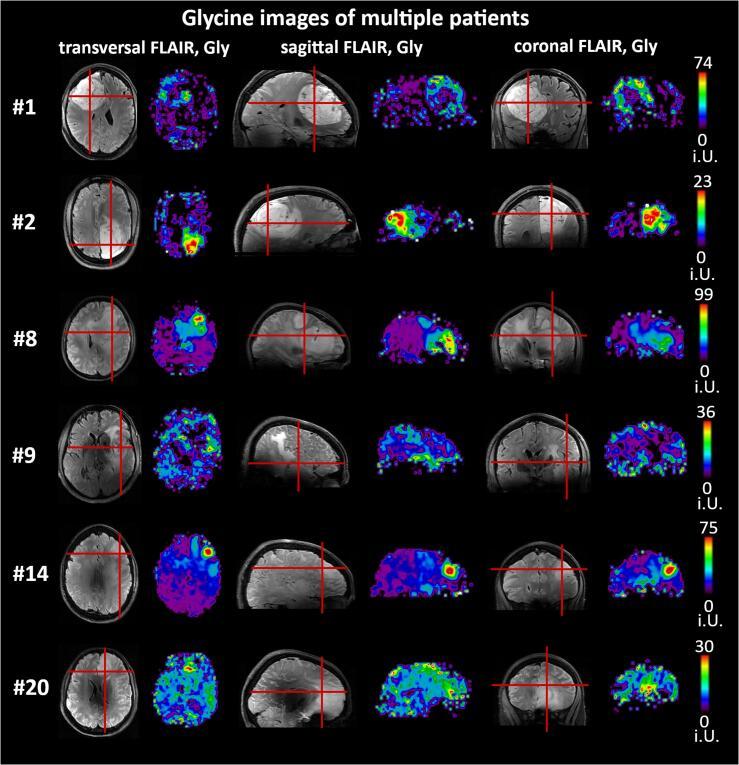

We preoperatively measured 23 patients with histologically verified HGGs (17 male, 8 female, age 53 ± 15) with an MRSI sequence based on concentric ring trajectories with a 64 × 64 × 39 measurement matrix, and a 3.4 × 3.4 × 3.4 mm nominal voxel volume in 15 min. Quantification used a basis-set of 17 components including N-acetyl-aspartate (NAA), total choline (tCho), total creatine (tCr), glutamate (Glu), glutamine (Gln), glycine (Gly) and 2-hydroxyglutarate (2HG). The resultant metabolic images were evaluated for their reliability as well as their quality and compared to spatially segmented tumor regions-of-interest (necrosis, contrast-enhanced, non-contrast enhanced + edema, peritumoral) based on clinical data and also compared to histopathology (e.g., grade, IDH-status).

Eighteen of the patient measurements were considered usable. In these patients, ten metabolites were quantified with acceptable quality. Gln, Gly, and tCho were increased and NAA and tCr decreased in nearly all tumor regions, with other metabolites such as serine, showing mixed trends. Overall, there was a reliable characterization of metabolic tumor areas. We also found heterogeneity in the metabolic images often continued into the peritumoral region. While 2HG could not be satisfyingly quantified, we found an increase of Glu in the contrast-enhancing region of IDH-wildtype HGGs and a decrease of Glu in IDH1-mutant HGGs.

We successfully demonstrated high-resolution 7T 3D-MRSI in HGG patients, showing metabolic differences between tumor regions and peritumoral tissue for multiple metabolites. Increases of tCho, Gln (related to tumor metabolism), Gly (related to tumor proliferation), as well as decreases in NAA, tCr, and others, corresponded very well to clinical tumor segmentation, but were more heterogeneous and often extended into the peritumoral region.

我们术前对 23 例经组织学证实的 HGG 患者(17 名男性,8 名女性,年龄 53±15 岁)进行了测量,使用基于同心环轨迹的 MRSI 序列,测量矩阵为 64×64×39,体素体积为 3.4×3.4×3.4mm,15 分钟内完成。定量分析使用包括 N-乙酰天冬氨酸(NAA)、总胆碱(tCho)、总肌酸(tCr)、谷氨酸(Glu)、谷氨酰胺(Gln)、甘氨酸(Gly)和 2-羟基戊二酸(2HG)在内的 17 个成分的基集。对代谢图像的可靠性、质量以及基于临床数据的肿瘤区域(坏死、增强、非增强+水肿、肿瘤周围)进行了评估,并与组织病理学(如分级、IDH 状态)进行了比较。

18 名患者的测量值被认为是可用的。在这些患者中,有 10 种代谢物的定量质量可以接受。几乎所有肿瘤区域的 Gln、Gly 和 tCho 增加,NAA 和 tCr 减少,而其他代谢物如丝氨酸则呈现混合趋势。总的来说,代谢肿瘤区域的特征具有可靠性。我们还发现代谢图像中的异质性通常延伸到肿瘤周围区域。虽然 2HG 不能令人满意地定量,但我们发现 IDH 野生型 HGG 中增强区的 Glu 增加,而 IDH1 突变型 HGG 中 Glu 减少。

我们成功地在 HGG 患者中展示了高分辨率 7T 3D-MRSI,显示了多种代谢物在肿瘤区域与肿瘤周围组织之间的代谢差异。tCho、Gln(与肿瘤代谢有关)、Gly(与肿瘤增殖有关)的增加,以及 NAA、tCr 和其他代谢物的减少,与临床肿瘤分割非常吻合,但更具异质性,且常常延伸至肿瘤周围区域。